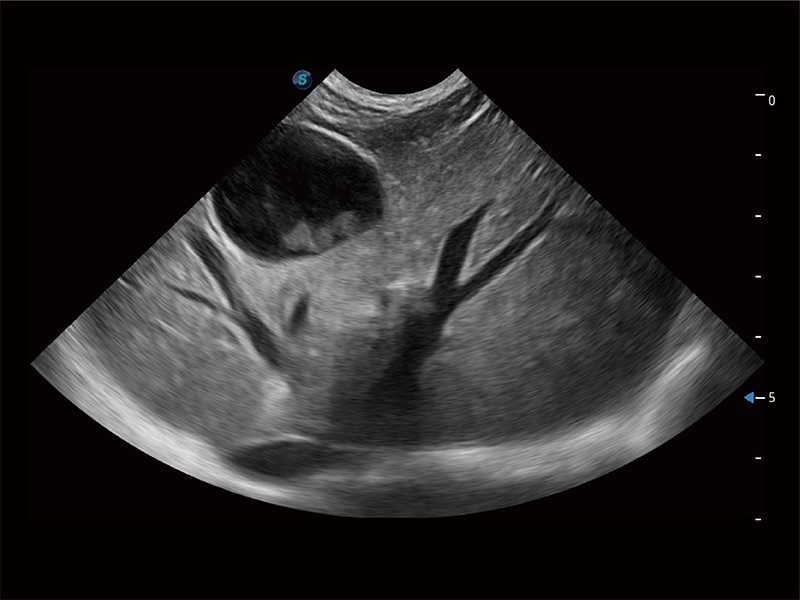

非线性融合造影成像充分利用谐波和基波信号,为难以观察的血流进行增强显像。可用于线阵、凸阵、微凸阵、相控阵探头。

ProPet 80 配备了丰富的心脏探头群、先进的成像技术和专业的心脏测量工具,可帮助动物医生为不同体型和生理结构的动物提供心脏和心肌功能的全面评估。

能够增加心肌组织与血流之间的区别。对于心脏扫查困难的动物,可提供更好的心内膜边界的显示。

ProPet 80 专为动物医生设计,对不同的动物体型和生理结构作出了针对性的优化。通过动物影像专用软件,可满足个性化的应用需求,帮助动物医生获得更精确的诊断数据。

ProPet 80 全新的动物超声智能软件和丰富的探头群,为动物医生提供了高清晰度和精细分辨率的图像,无论在宠物、马科、畜牧还是实验室动物等应用中都可以轻松应对,为您的日常工作带来满意的体验。